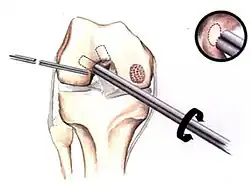

Full thickness lesions

The three methods most commonly used in treating full thickness lesions are arthroscopic drilling, abrasion, and microfracturing.

Similar to OATS, arthroscopic articular cartilage paste grafting is a surgical procedure offering cost-effective, long-lasting results for stage IV lesions. A bone and cartilage paste derived from crushed plugs of the non-weight-bearing intercondylar notch can achieve pain relief, repair damaged tissue, and restore function.[61]